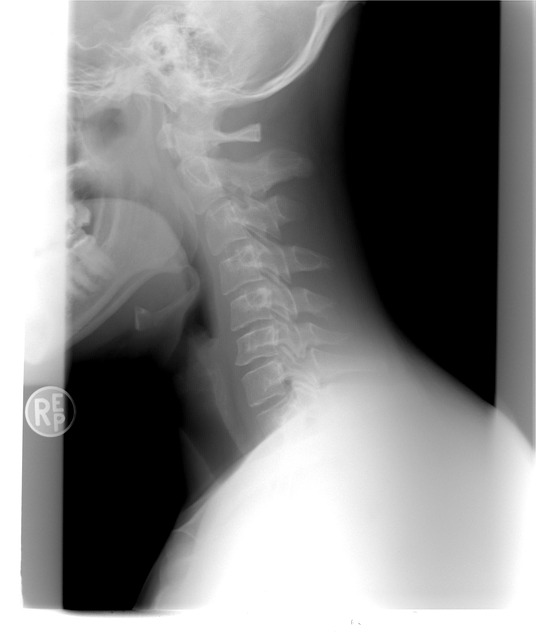

갑상선은 우리 목에 위치해 있고, 신진대사에 필요한 갑상선 호르몬을 분비하는 내분비기관입니다.

그래서 갑상선의 문제를 쉽게 넘어가선 되는데, 그 중 대표적인 증상이 갑상선이 있을 위치의 목 부음 증상입니다.

갑상선 목부음은 갑상선종으로 칭하는데